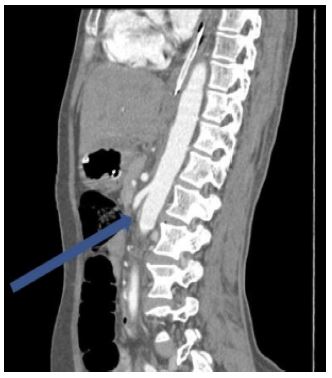

363 out of 388 cases showed a normal trifurcation pattern of the coeliac trunk (Uflacker I) representing 93.5 % of the total cases. Among the commonest anomalies among the coeliac, trunk variations were Type V Uflacker in the form of the gastro-splenic trunk with CHA arising from the aorta (most common anomaly) (Figure 1) representing 20 % of cases followed by Uflacker types II, III, IV & VIII (Figure 2) each type found in 4% of cases.

Figure 1: Axial CT cuts showing gastrosplenic trunk (red arrow) with CHA (white arrow) separately arising from the aorta.